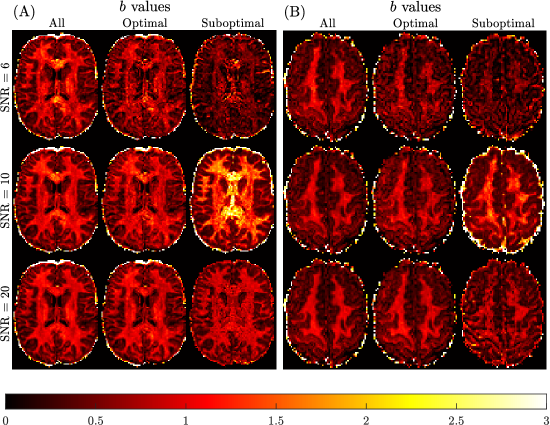

Figure 9 presents the qualitative findings for two subjects generated using all, optimal and sub-optimal b-value samplings with SNR = 666 (3 non-collinear directions, 6 measurements), 101010 (8 non-collinear directions, 16 measurements) and 202020 (32 non-collinear directions, 64 measurements) DW-MRI data. The quality of the mean kurtosis map improves with increasing SNR, and also by optimising b-value sampling. Optimal sampling at SNR = 101010 is qualitatively comparable to the SNR = 202020 optimal sampling result, and to the benchmark sub-diffusion results in Figure 6.

Refer to caption

Figure 9: Spatially resolved maps of mean kurtosis shown for two example slices and two different subjects, Subject 3 rescan slice 71 (Panel A) and Subject 5 slice 74 (Panel B), based on SNR reduction of the Connectome 1.0 DW-MRI data. Individual maps were generated using the sub-diffusion model framework (Ksuperscript𝐾K^{*}), considering optimal and sub-optimal four non-zero b-value sampling schemes. Here, two b-values with Δ=19 msΔ19 ms\Delta=19\text{ ms} and two b-values with Δ=49 msΔ49 ms\Delta=49\text{ ms} were selected for each case. The optimal b-values were chosen as the best for each SNR shown in Table 1. The sub-optimal b-values were chosen to have an R2=0.3,0.45,0.5superscript𝑅20.30.450.5R^{2}=0.3,0.45,0.5 to be about half of the maximum R2superscript𝑅2R^{2}, for SNR =6absent6=6 (b=800,1500,200,2300 s/mm2𝑏80015002002300 ssuperscriptmm2b=800,1500,200,2300\text{ s}/\text{mm}^{2}), SNR =10absent10=10 (b=1500,3450,6750,13500 s/mm2𝑏15003450675013500 ssuperscriptmm2b=1500,3450,6750,13500\text{ s}/\text{mm}^{2}) and SNR =20absent20=20 (b=3450,4750,2300,4250 s/mm2𝑏3450475023004250 ssuperscriptmm2b=3450,4750,2300,4250\text{ s}/\text{mm}^{2}), respectively. The benchmark kurtosis map is provided in Figure 6.

Quantitative verification of the qualitative observations are provided in Table 3. Significant differences in brain region-specific mean kurtosis values occur at the SNR =6absent6=6 level, which are not apparent when SNR =10absent10=10 or 202020 data with optimal b-value sampling were used. The average errors are relative errors compared to the benchmark kurtosis values reported in Table 2. When using optimal b-values, average errors range from 22% to 43% at SNR = 6, from 13% to 43% at SNR = 10, and from 8% to 20% at SNR = 20, across brain regions. When using sub-optimal b-values, average errors range from 47% to 57% at SNR = 6, from 24% to 102% at SNR = 10, and from 27% to 72% at SNR = 20. Also, the brain region-specific CV for mean kurtosis was not found to change markedly when SNR =10absent10=10 or 202020 data were used to compute Ksuperscript𝐾K^{*}. The result of reducing the SNR to 666 leads to an approximate doubling of the CV for each brain region. These findings confirm that with optimal b-value sampling, the data quality can be reduced to around the SNR =10absent10=10 level, without a significant impact on the region-specific mean kurtosis estimates derived using the sub-diffusion model.